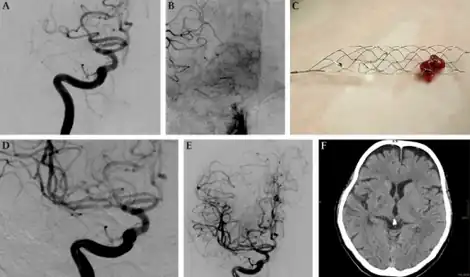

| Mechanical thrombectomy using a Solitaire stent-a)Injection of internal carotid artery shows embolic occlusion b)leptomeningeal collaterals visualized c)solitaire stent loaded with thrombus d,e)DSA with injection of right ICA f) 22 months after there is a small post-ischemic scar | |